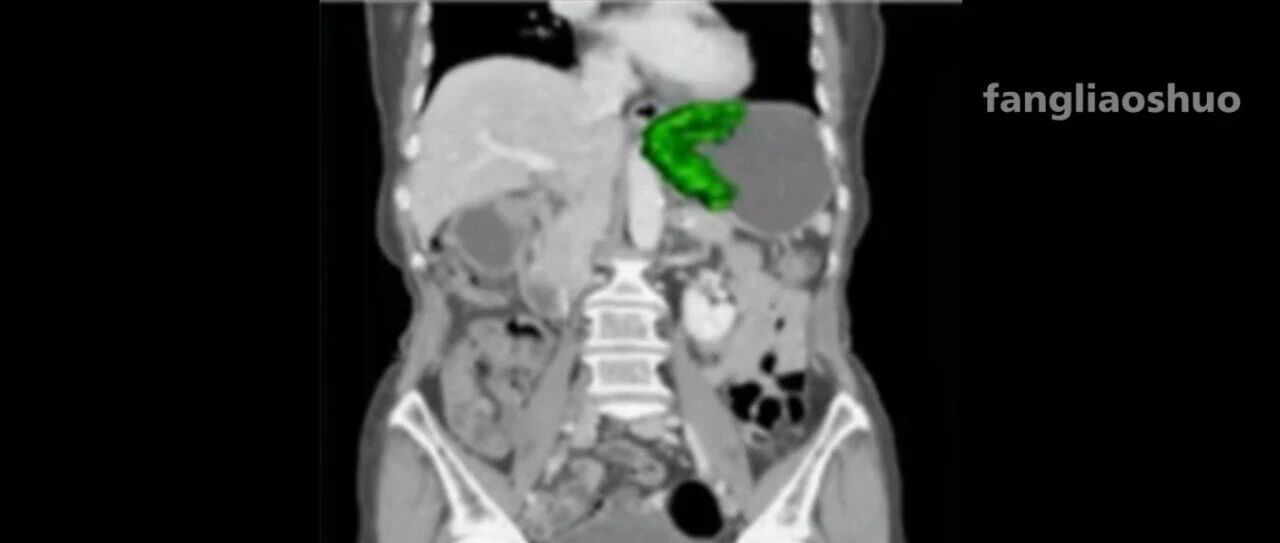

![]() TNM分期目录 病理三人行 发布时间2026/01/01 23:00:45 | - | - | - | 35 | 更多 |